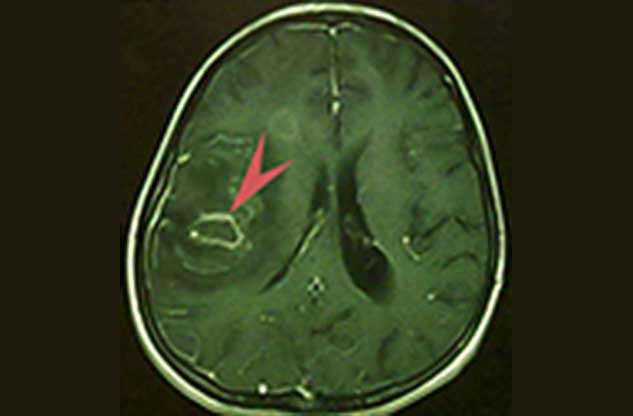

ब्रेन टीबी का निदान (diagnosed of Brain TB)

शुरुआत में डॉक्टर आपका शारीरिक परीक्षण करता है, जिसमें वह आपके लक्षण, मेडिकल इतिहास के बारे में पूछेगा। अगर आपके डॉक्टर को ब्रेन टीबी का संदेह होगा, तो वह आपको निम्न टेस्ट कराने की सलाह दे सकता है।

- सिर का सीटी स्कैन (CT Scan)